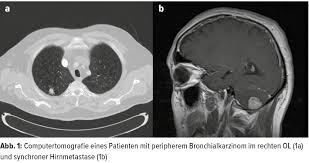

Ausgabe 4 2011 Lungenkrebs Diagnostik Und Therapie Einer Vermeidbaren Tumorerkrankung